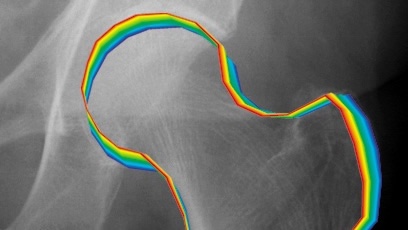

Our innovative, interdisciplinary research spans a wide range of activities, from discovery science to understand the causes of arthritis, translational preclinical research to develop new treatment strategies, development of novel imaging technologies to improve diagnosis and treatment, clinical and population studies to understand risk factors and population perspectives, to randomised controlled clinical trials to determine efficacy of new treatment paradigms.